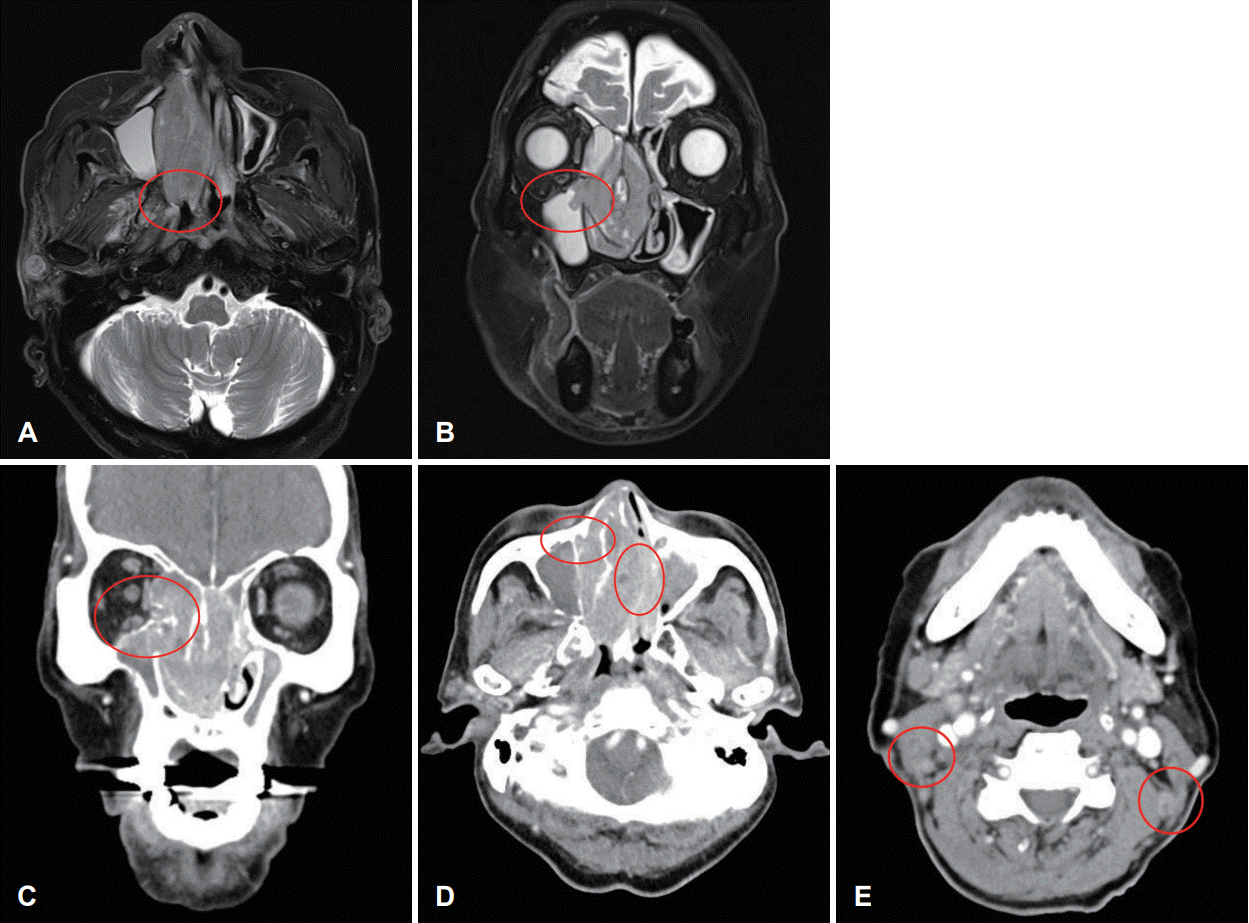

Fig. 2.